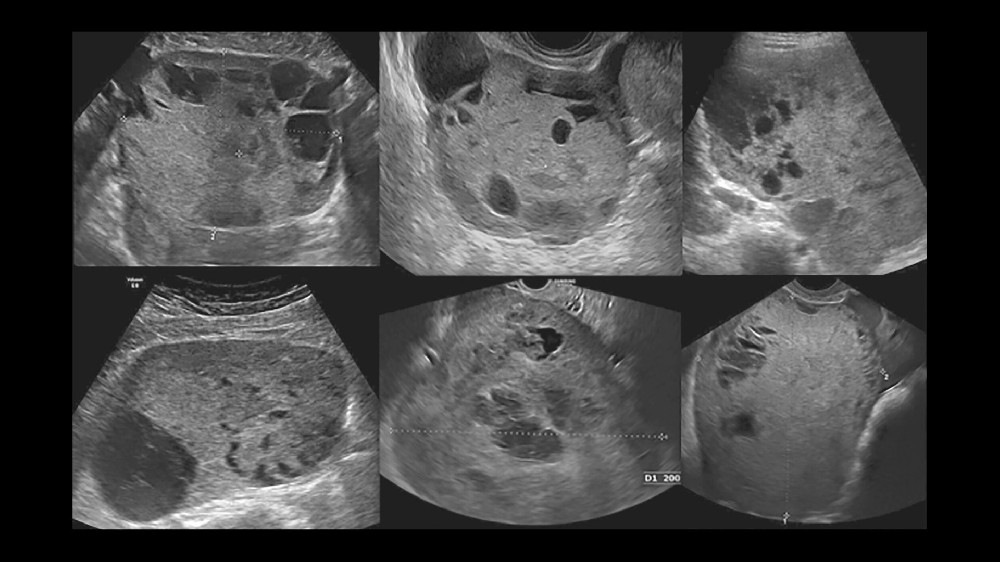

影像和活檢可提供確切證據,以進行精確的分期和治療規劃

女性卵巢增大或骨盆不適,通常會因為初期症狀不顯著而導致延遲診斷

病變通常較小,直徑小於 2-3 公分,完全定位,無可察覺的淋巴受累

腫瘤中度擴大,約 3-5 公分,有證據顯示區域淋巴受累,但無遠端轉移

腫瘤大小經常超過 5 公分,附近有廣泛的淋巴、區域器官浸潤或轉移。